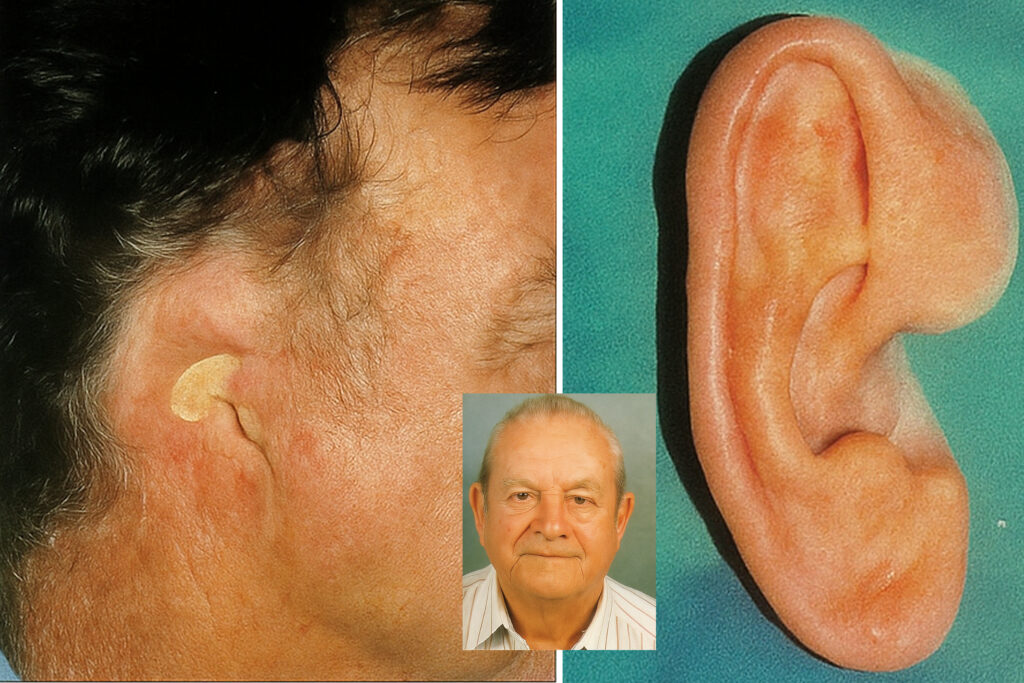

Dr. Sumaya is a well-established and highly experienced Prosthodontist, Implantologist, and Maxillofacial Prosthodontist, with a distinguished career dedicated to advanced restorative and aesthetic dentistry. With a strong foundation in prosthodontics and oral rehabilitation, Dr. Sumaya also specializes in cosmetic dentistry, including veneers, laminates, and smile design, offering patients personalized and transformative dental solutions.

With over 9 years of clinical expertise, Dr. Sumaya has successfully managed a wide range of complex cases — from full-mouth rehabilitation and implant-supported prostheses to the intricate reconstruction of maxillofacial defects due to trauma, congenital anomalies, or oncologic surgery.

Known for a keen eye for detail and artistic precision, Dr. Sumaya integrates function with aesthetics, helping patients achieve confident, natural-looking smiles. Their approach combines cutting-edge technology with the latest techniques in digital smile design and cosmetic restorations.